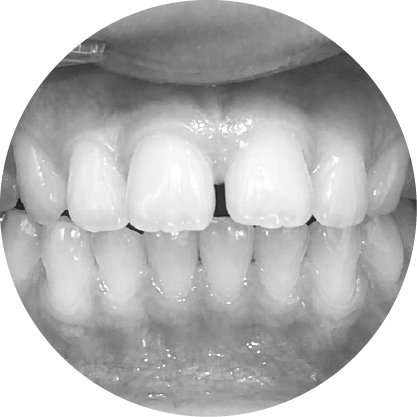

ช่องว่างระหว่างฟัน (Diastema)

การปิดช่องว่างระหว่างฟัน เพื่อรอยยิ้มที่สมบูรณ์แบบ

"ช่องว่างระหว่างฟันหรือไดแอสเทมา หมายถึงช่องว่างระหว่างฟันที่เห็นได้ชัด ซึ่งอาจเป็นปัญหาทางความงามสำหรับหลายๆ คนการจัดฟันสามารถปิดช่องว่าง เหล่านี้ได้อย่างมีประสิทธิภาพทำให้มีรอยยิ้มที่สม่ำเสมอและสวยงาม"

ตัวอย่างในชีวิตจริง